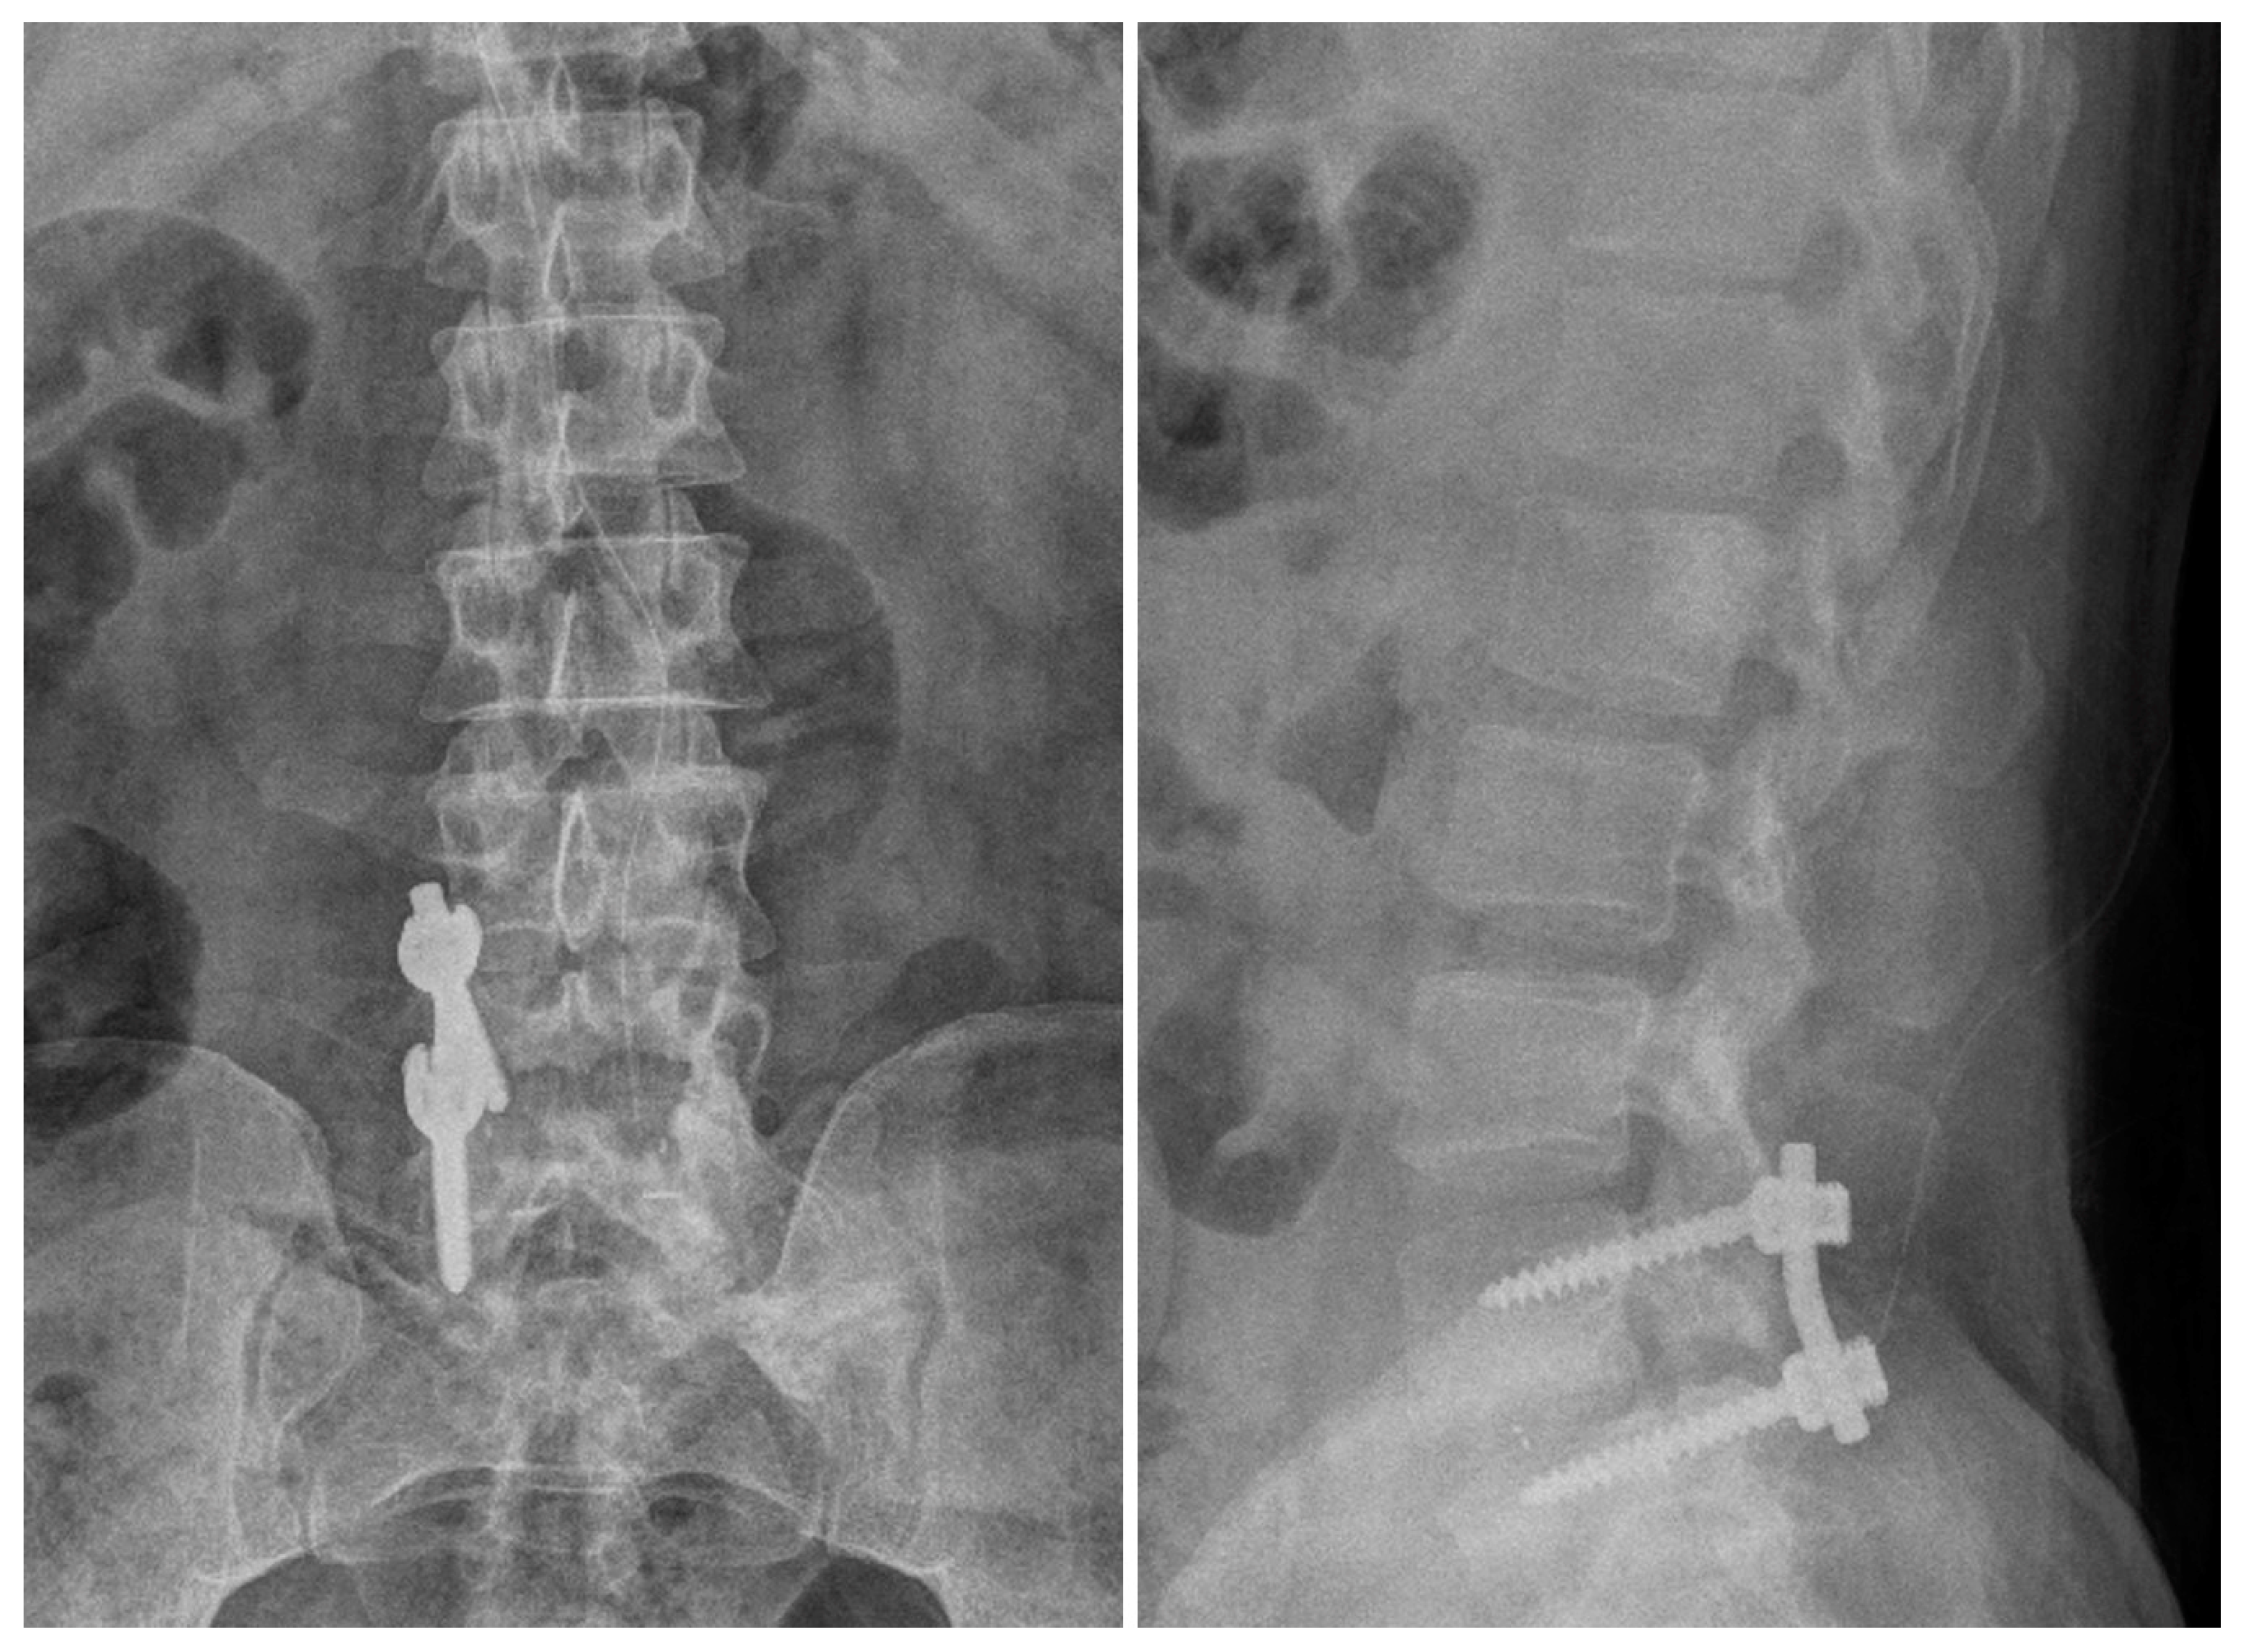

2.2. Case 2